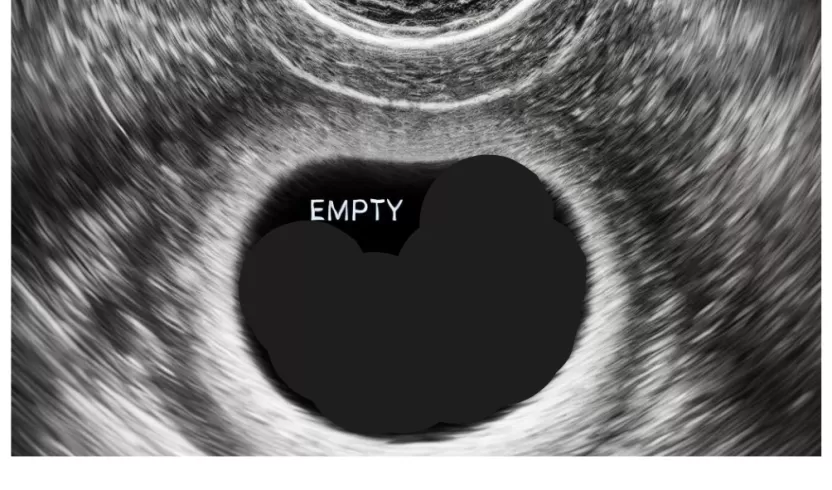

- ومن الجدير بالذكر أن وجود كيس الحمل لا يؤكد أن هناك بالتأكيد جنين، ففي الكيس من الأحيان يظهر كيس الحمل، ولكن يكون فارغ بمعنى أنه لا يوجد بداخله جنين وهو ما يسمى بالحمل الكاذب.

شكل كيس الحمل الفارغ بالسونار

متى يظهر الحمل في كيس الحمل الفارغ أو الحمل اللاجنيني وأسباب حدوثه؟

الحمل اللاجنيني يتشابه إلى حد كبير مع الحمل العادي، من حيث أعراض الظهور أو علامات حدوث الحمل، ولكن يقصد بالحمل اللاجنيني هو أن كيس الجنين يظهر ولكن يكون فارغ أو ما يعرف بالحمل الكاذب، ولهذا سنتعرف على الحالة التي تؤدي إلى حدوث اللاجنيني وأسبابه:

- عند إجراء فحص السونار المهبلي أو البطني سيتأكد الطبيب أن هذا حمل كاذب أو فارع أو كما يطلق عليه في الطب مصطلح حمل لاجنيني.